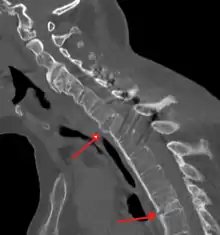

Imaging

X-rays

The earliest changes demonstrable by plain X-ray shows erosions and sclerosis in sacroiliac joints. Progression of the erosions leads to widening of the joint space and bony sclerosis. X-ray spine can reveal squaring of vertebrae with bony spur formation called syndesmophyte. This causes the bamboo spine appearance. A drawback of X-ray diagnosis is the signs and symptoms of AS have usually been established as long as 7–10 years prior to X-ray-evident changes occurring on a plain film X-ray, which means a delay of as long as 10 years before adequate therapies can be introduced.[24]

CT scan showing bamboo spine in ankylosing spondylitis